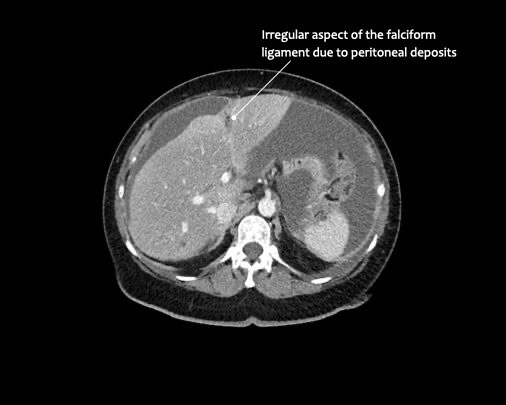

- Dây chằng liềm

Ở vùng bụng trên, cơ hoành và dây chằng liềm cần được chú ý đặc biệt.

Các vị trí điển hình khác bao gồm rãnh cạnh đại tràng, túi cùng trực tràng-bàng quang hoặc trực tràng-tử cung, dây chằng liềm và mặt bụng của cơ hoành.